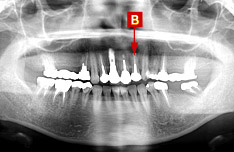

治療後のパノラマX線写真

歯を抜いたところに、1本インプラント治療を行いました。[B]

根だけでなく周囲の骨にも一部吸収がみられましたが、経過は良好で、冠せ物と歯ぐきの境目も自然に仕上がりました。患者さんにも「周りの歯がほとんど健康な歯なので目立つのではと心配だったが、自分の元々の歯のようで、まったく違和感がない」と喜んでいただけました。